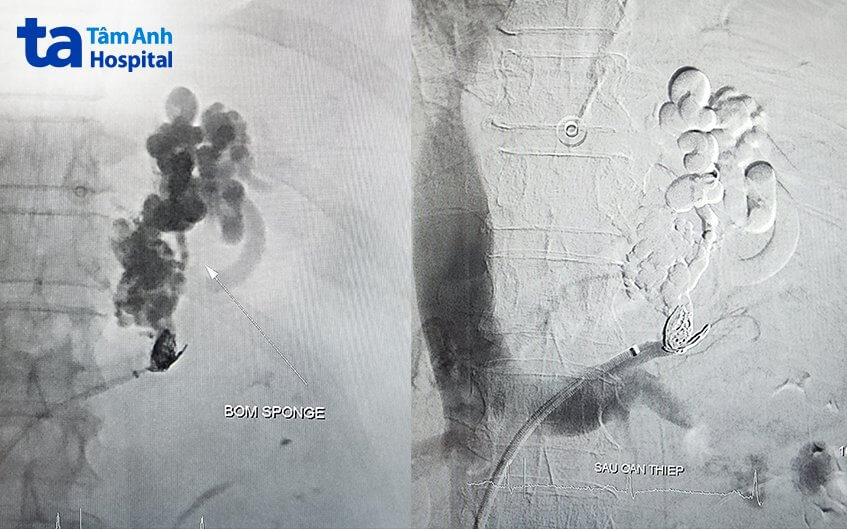

Ê kíp can thiệp đưa dụng cụ siêu nhỏ đi trong lòng mạch từ tĩnh mạch đùi phải, di chuyển đến vị trí búi giãn tĩnh mạch, sau đó bơm vật liệu để bít tắc mạch. Bệnh nhân chỉ cần gây tê vùng bẹn đùi phải và tỉnh táo trong suốt quá trình. Sau can thiệp, toàn bộ búi giãn tĩnh mạch gây xuất huyết được bít tắc thành công. Bệnh nhân hết xuất huyết, dự kiến xuất viện sau 5 ngày và cần tái khám, tiếp tục điều trị bệnh nền.

TS.BS Phan Thị Xuân, Trưởng khoa hồi sức tích cực, cho biết xuất huyết tiêu hóa do vỡ giãn tĩnh mạch dạ dày là biến chứng nguy hiểm của bệnh xơ gan nặng kèm theo tình trạng tăng áp lực tĩnh mạch cửa. Đây là bệnh cảnh không phổ biến, tỷ lệ tử vong cao, khoảng 45%. Phương pháp tắc búi giãn tĩnh mạch phình vị ngược dòng, với sự hỗ trợ của máy móc và dụng cụ can thiệp hiện đại, mang lại hiệu quả cao, rút ngắn thời gian thực hiện, giảm tai biến cho người bệnh. Tỷ lệ tái xuất huyết dưới 5%.